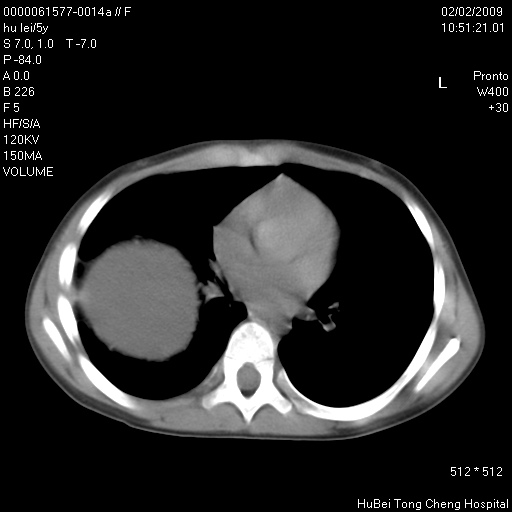

标题: PED1732:M5Y,右肺囊性占位!

患者:男,5。无明显不适,拍胸片考虑右肺囊肿。

行ct扫描,图象如下:

考虑支气管囊肿或皮样囊肿

考虑右肺支气管源性肺囊肿

肺囊肿---不排除淋巴管瘤可能